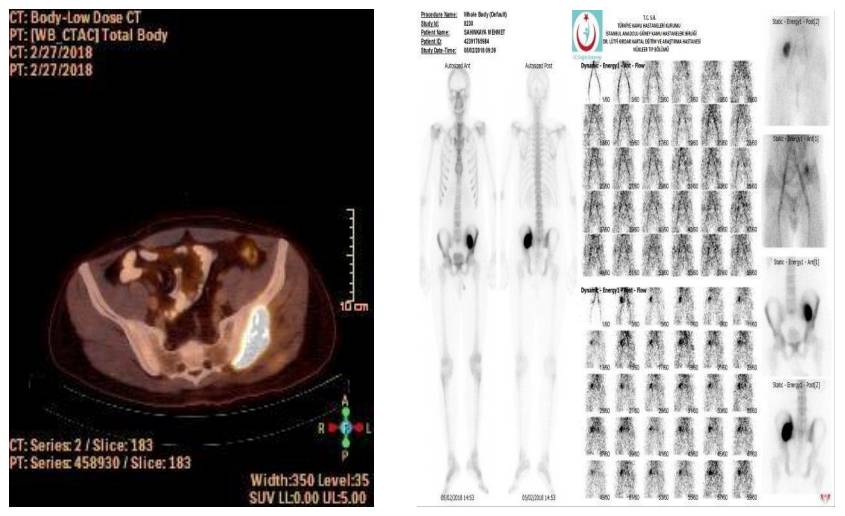

- İğne biyopsisi osteosarkom olarak gelen hastanın taramalarında metastaz saptanmadı

Ameliyat Öncesi: PET-CT ve sintigrafi’de artmış yoğun aktivite görülmekte